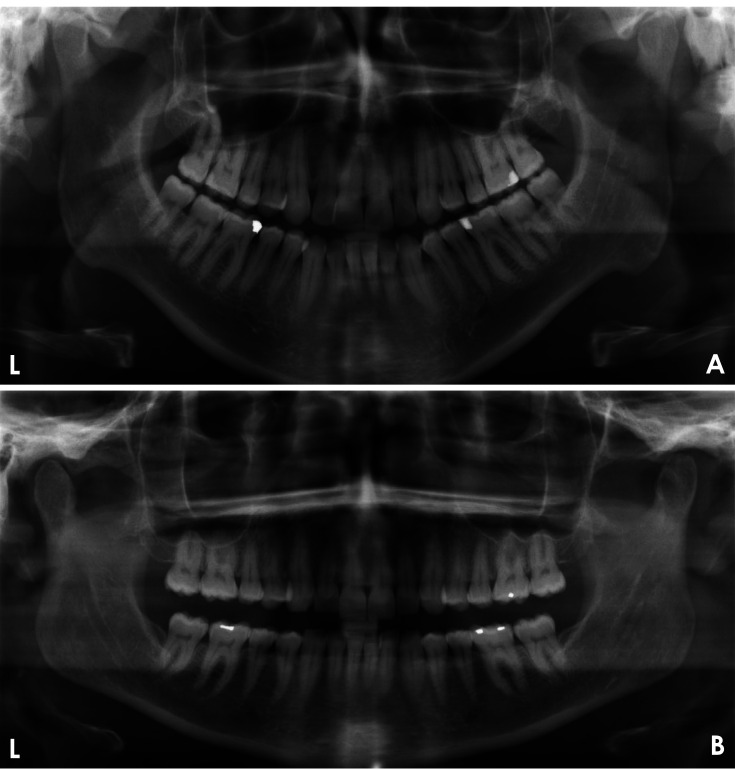

Materials and methods: This study aimed to develop a deep learning (DL)-based model for evaluating the quality of dental panoramic radiographs. A dataset of 1,000 panoramic images, collected from 2018 to 2023, was assessed by 2 trained dentists using predefined grading criteria for contrast/density, artifact presence, coverage area, patient positioning, and overall quality. These expert-annotated scores were used as the ground truth to train and validate 5 YOLOv8 classification models, each targeting a specific quality criterion. The models' performance was evaluated on a separate test set using performance metrics.